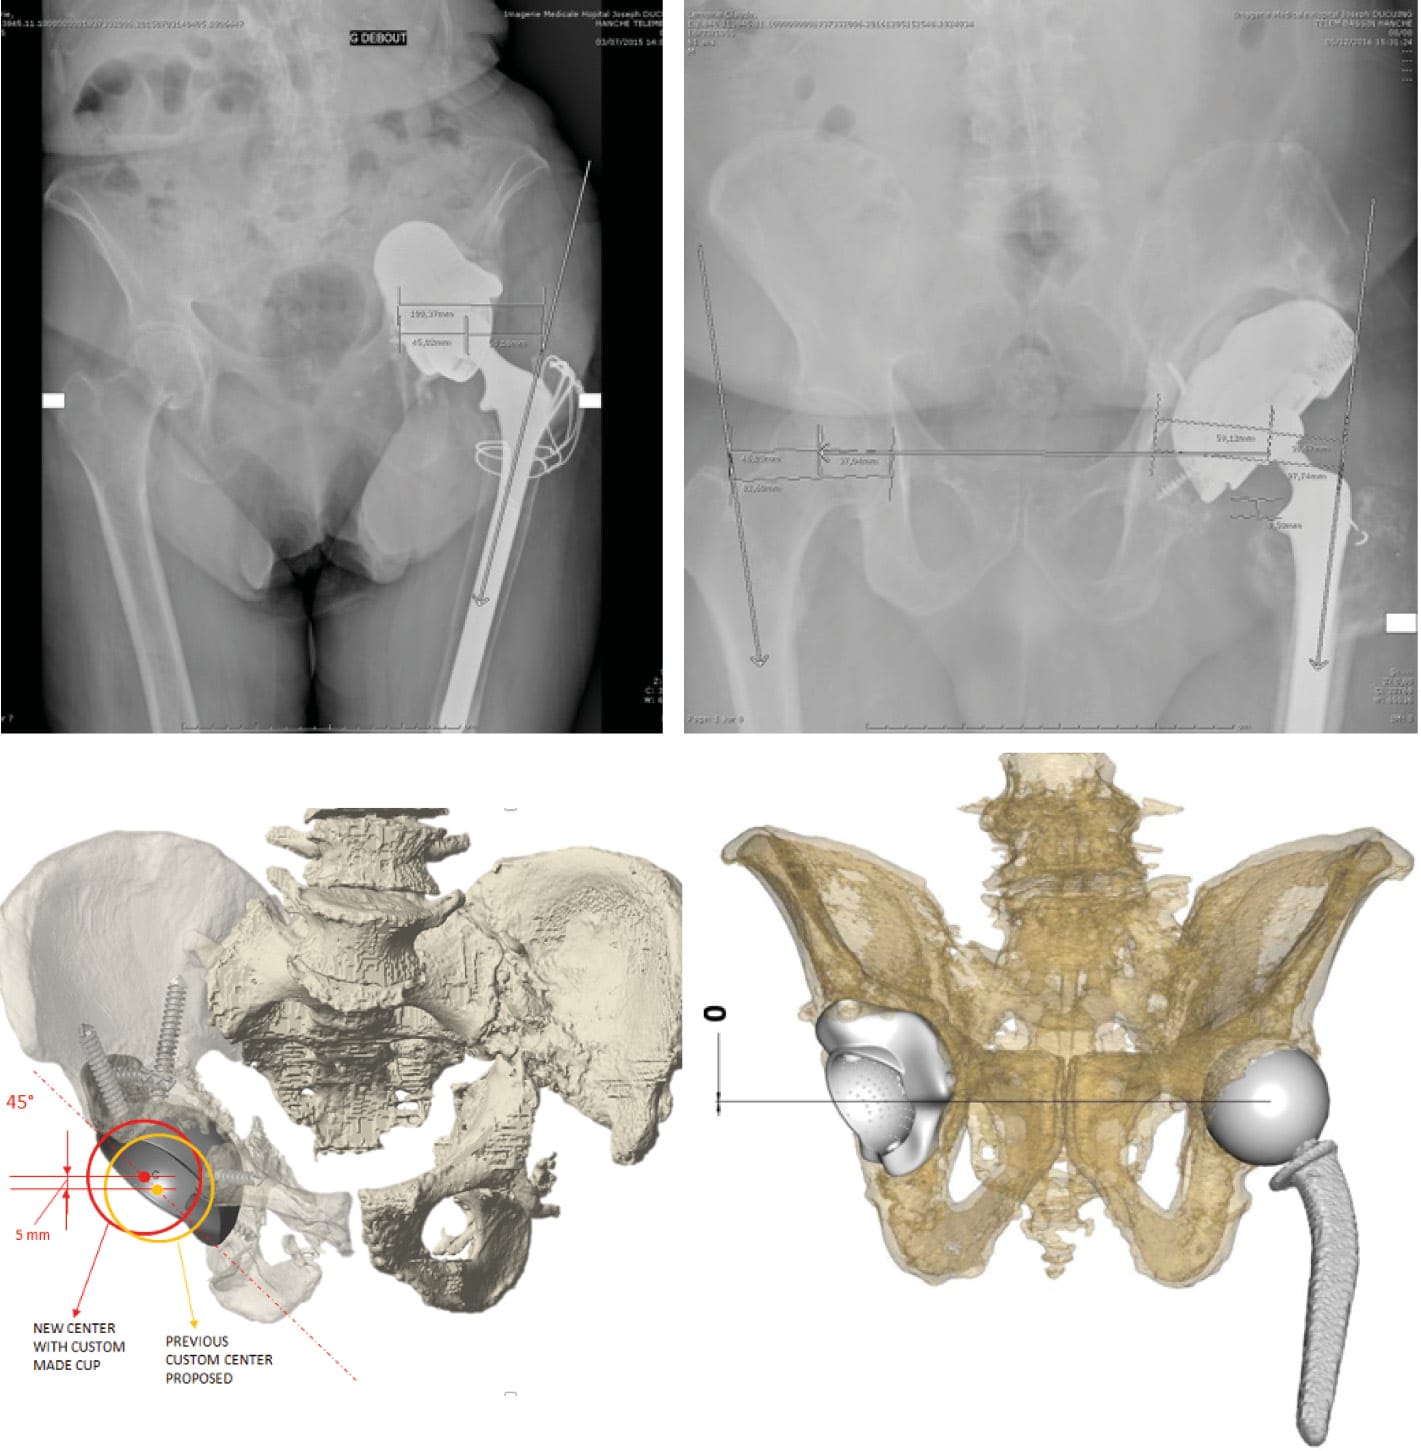

Although the various classifications published, as we have seen, can be cross-referenced to determine the geometry of defects and define custom implant designs, they are not always particularly informative when planning how to anchor the implant (Figure 6, 7 & 8). In this respect, perioperative adaptation is often needed.

From our perspective, the design of the 3D-printed implant must respect both the dip of the anterior wall and the elevation of the posterior wall. This design is able to reduce anterior and posterior impingement, especially if the orientation of the native acetabulum or the reconstruction imperatives mean fitting the 3D-printed component in a relatively neutral position. The combination with anatomic DM cups is our preferred option. During surgery the relative position of both components must be adjusted in real time (Figure 12).

- Improved management of the restoration of the centre of rotation in the planning stages (Figure 14)